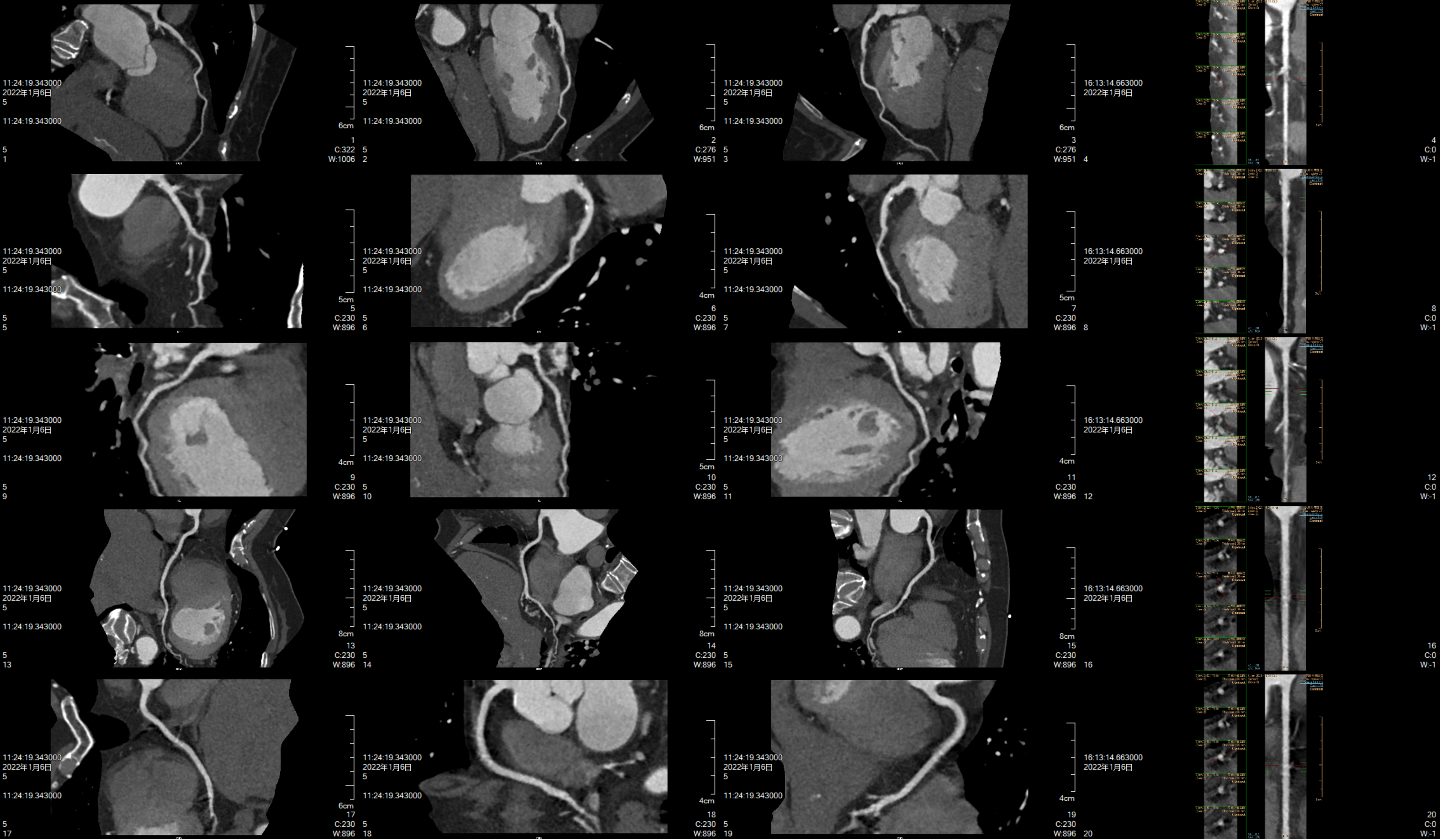

最后附上部分仪器拍摄图片,由于微信公众号上传图片进行了部分压缩,实际图像会比下面更清晰。

心脏冠脉CTA